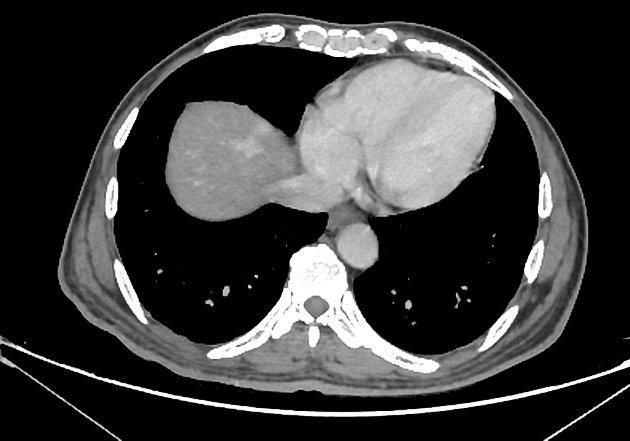

Axial C+ portal venous phase

CT•Axial C+ portal venous phase•1 / 23

- Tăng đậm nhanh của tĩnh mạch cửa chính mà không có ngấm thuốc thì động mạch ở tĩnh mạch lách hoặc tĩnh mạch mạc treo tràng trên, gợi ý hình thành thông động-tĩnh mạch (arterio-portal fistula).

- Đã tiêu diệt thành công tổn thương khu trú ở phân thuỳ VII với không còn mô sống sót.

- "Tăng đậm sớm tĩnh mạch cửa mà không có ngấm thuốc ở tĩnh mạch lách hoặc tĩnh mạch mạc treo tràng trên là dấu hiệu hình ảnh đặc trưng của thông động-tĩnh mạch."